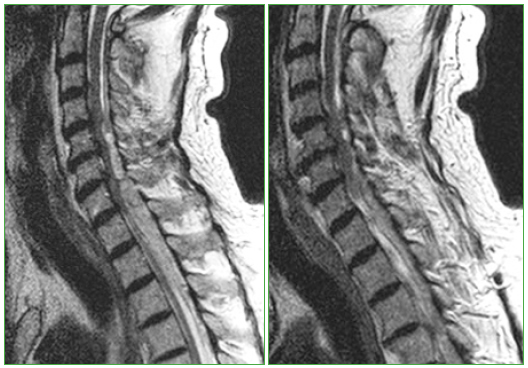

El hematoma epidural espontáneo es una entidad muy poco frecuente que supone una urgencia neurológica. Su presentación es muy variable, desde un dolor de espalda hasta una tetraplejia, según la gravedad y el nivel de compresión. Se comunica el caso de un paciente cardiópata de 71 años, tratado con acenocumarol, que presentó un hematoma epidural de modo espontáneo. Al inclinarse hacia el suelo, el paciente, que no tenía síntomas, sufrió un dolor brusco cervical seguido de debilidad en los miembros superiores e inferiores. Ante la sospecha clínica de una compresión medular, se decide realizar una resonancia magnética de urgencia, que mostró un hematoma de localización epidural con extensión desde C4 hasta T8. El diagnóstico urgente y el tratamiento de descompresión precoz son fundamentales para reducir al mínimo los daños neurológicos posteriores permanentes. AbstractSpontaneous spinal epidural hematoma is an uncommon condition and a neurological emergency. The clinical presentation of this type of hematoma is very variable, ranging from a backache up to a quadriplegia, according to the severity and the site of compression. Here, we discuss the clinical case of a 71-year-old patient with heart problems, under previous treatment with acenocumarol, that suffered a spontaneous epidural hematoma. The patient, previously asymptomatic, presented, sudden cervical pain when he bent over, followed by weakness in the lower and the upper limbs. Due to the clinical suspicion, an emergency MRI was performed, showing an epidural hematoma extending from C4 to T8. Early diagnosis and decompressive treatment are mandatory to minimize permanent neurological damage.Descargas